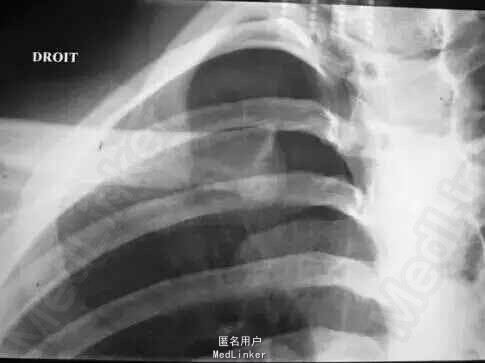

主诉骑摩托车摔伤后胸前部疼痛2小时。 病史:来院前2小时骑摩托车时不慎摔伤,伤后胸前部疼痛,左肩活动时疼痛加重,急诊来院,行拍片检查发现左胸锁关节脱位入院。

查体:胸前部略肿胀,左侧胸锁关节处隆起,触痛,可触及浮动感,左肩活动时疼痛加重,余未见异常。 辅检:门诊X线片:左侧胸锁关节脱位